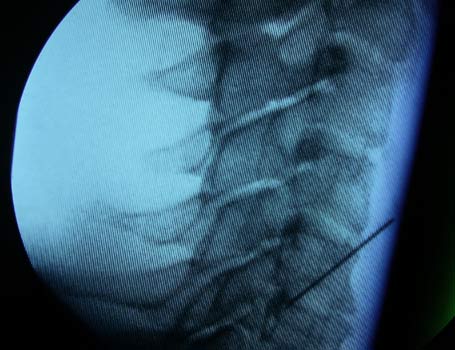

1. Mittels eines C-Bogens

(Röntgengerät) wird im Operationssaal unter sterilen Bedingungen

die Wirbelsäule durchleuchtet wie bei einer Röntgenaufnahme – nur

mit geringerer Strahlenbelastung. Das Gerät zeigt die Stelle

an, die den Schmerz verursacht. An dieser Stelle wird gezielt eine

Injektion mit Medikamenten vorgenommen, die die gereizten Nervenstrukturen

beruhigen. Dadurch wird der Schmerz deutlich und schnell besser

und der Patient kann sich wieder normal bewegen. Dadurch können

auch viele Bandscheibenoperationen vermieden werden!